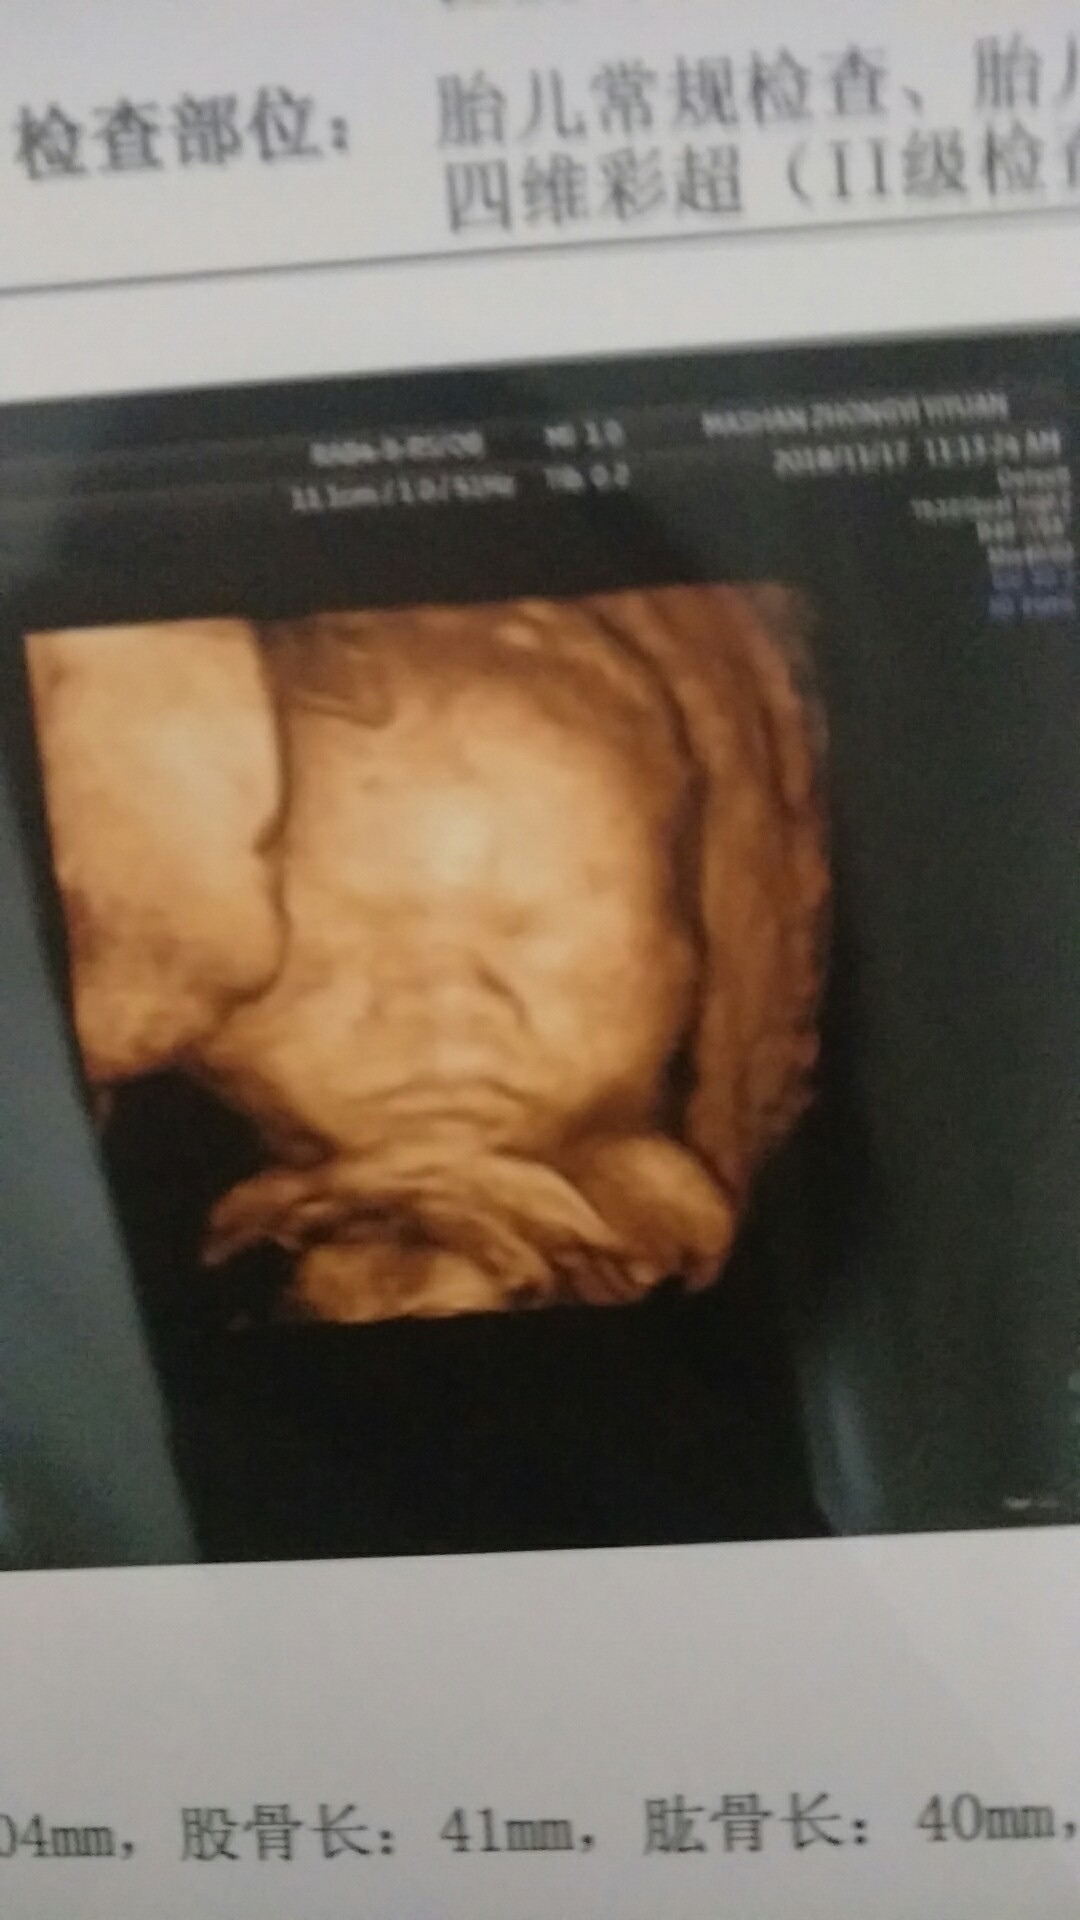

孕25周+6天

我宝宝做四维的时候也是动的特别快